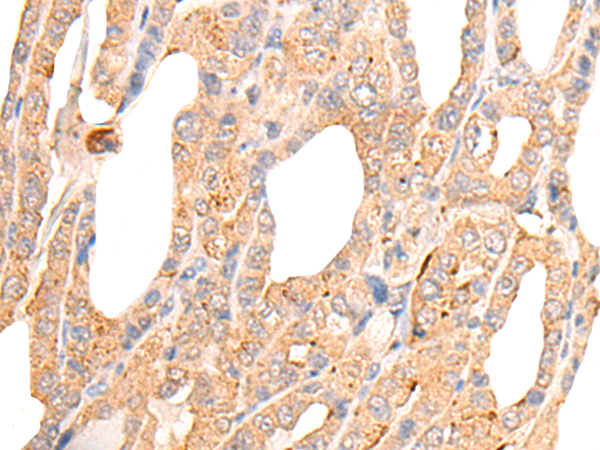

IHC positive control:

Human thyroid cancer and Human ovarian cancer

IHC Recommend dilution:

25-100